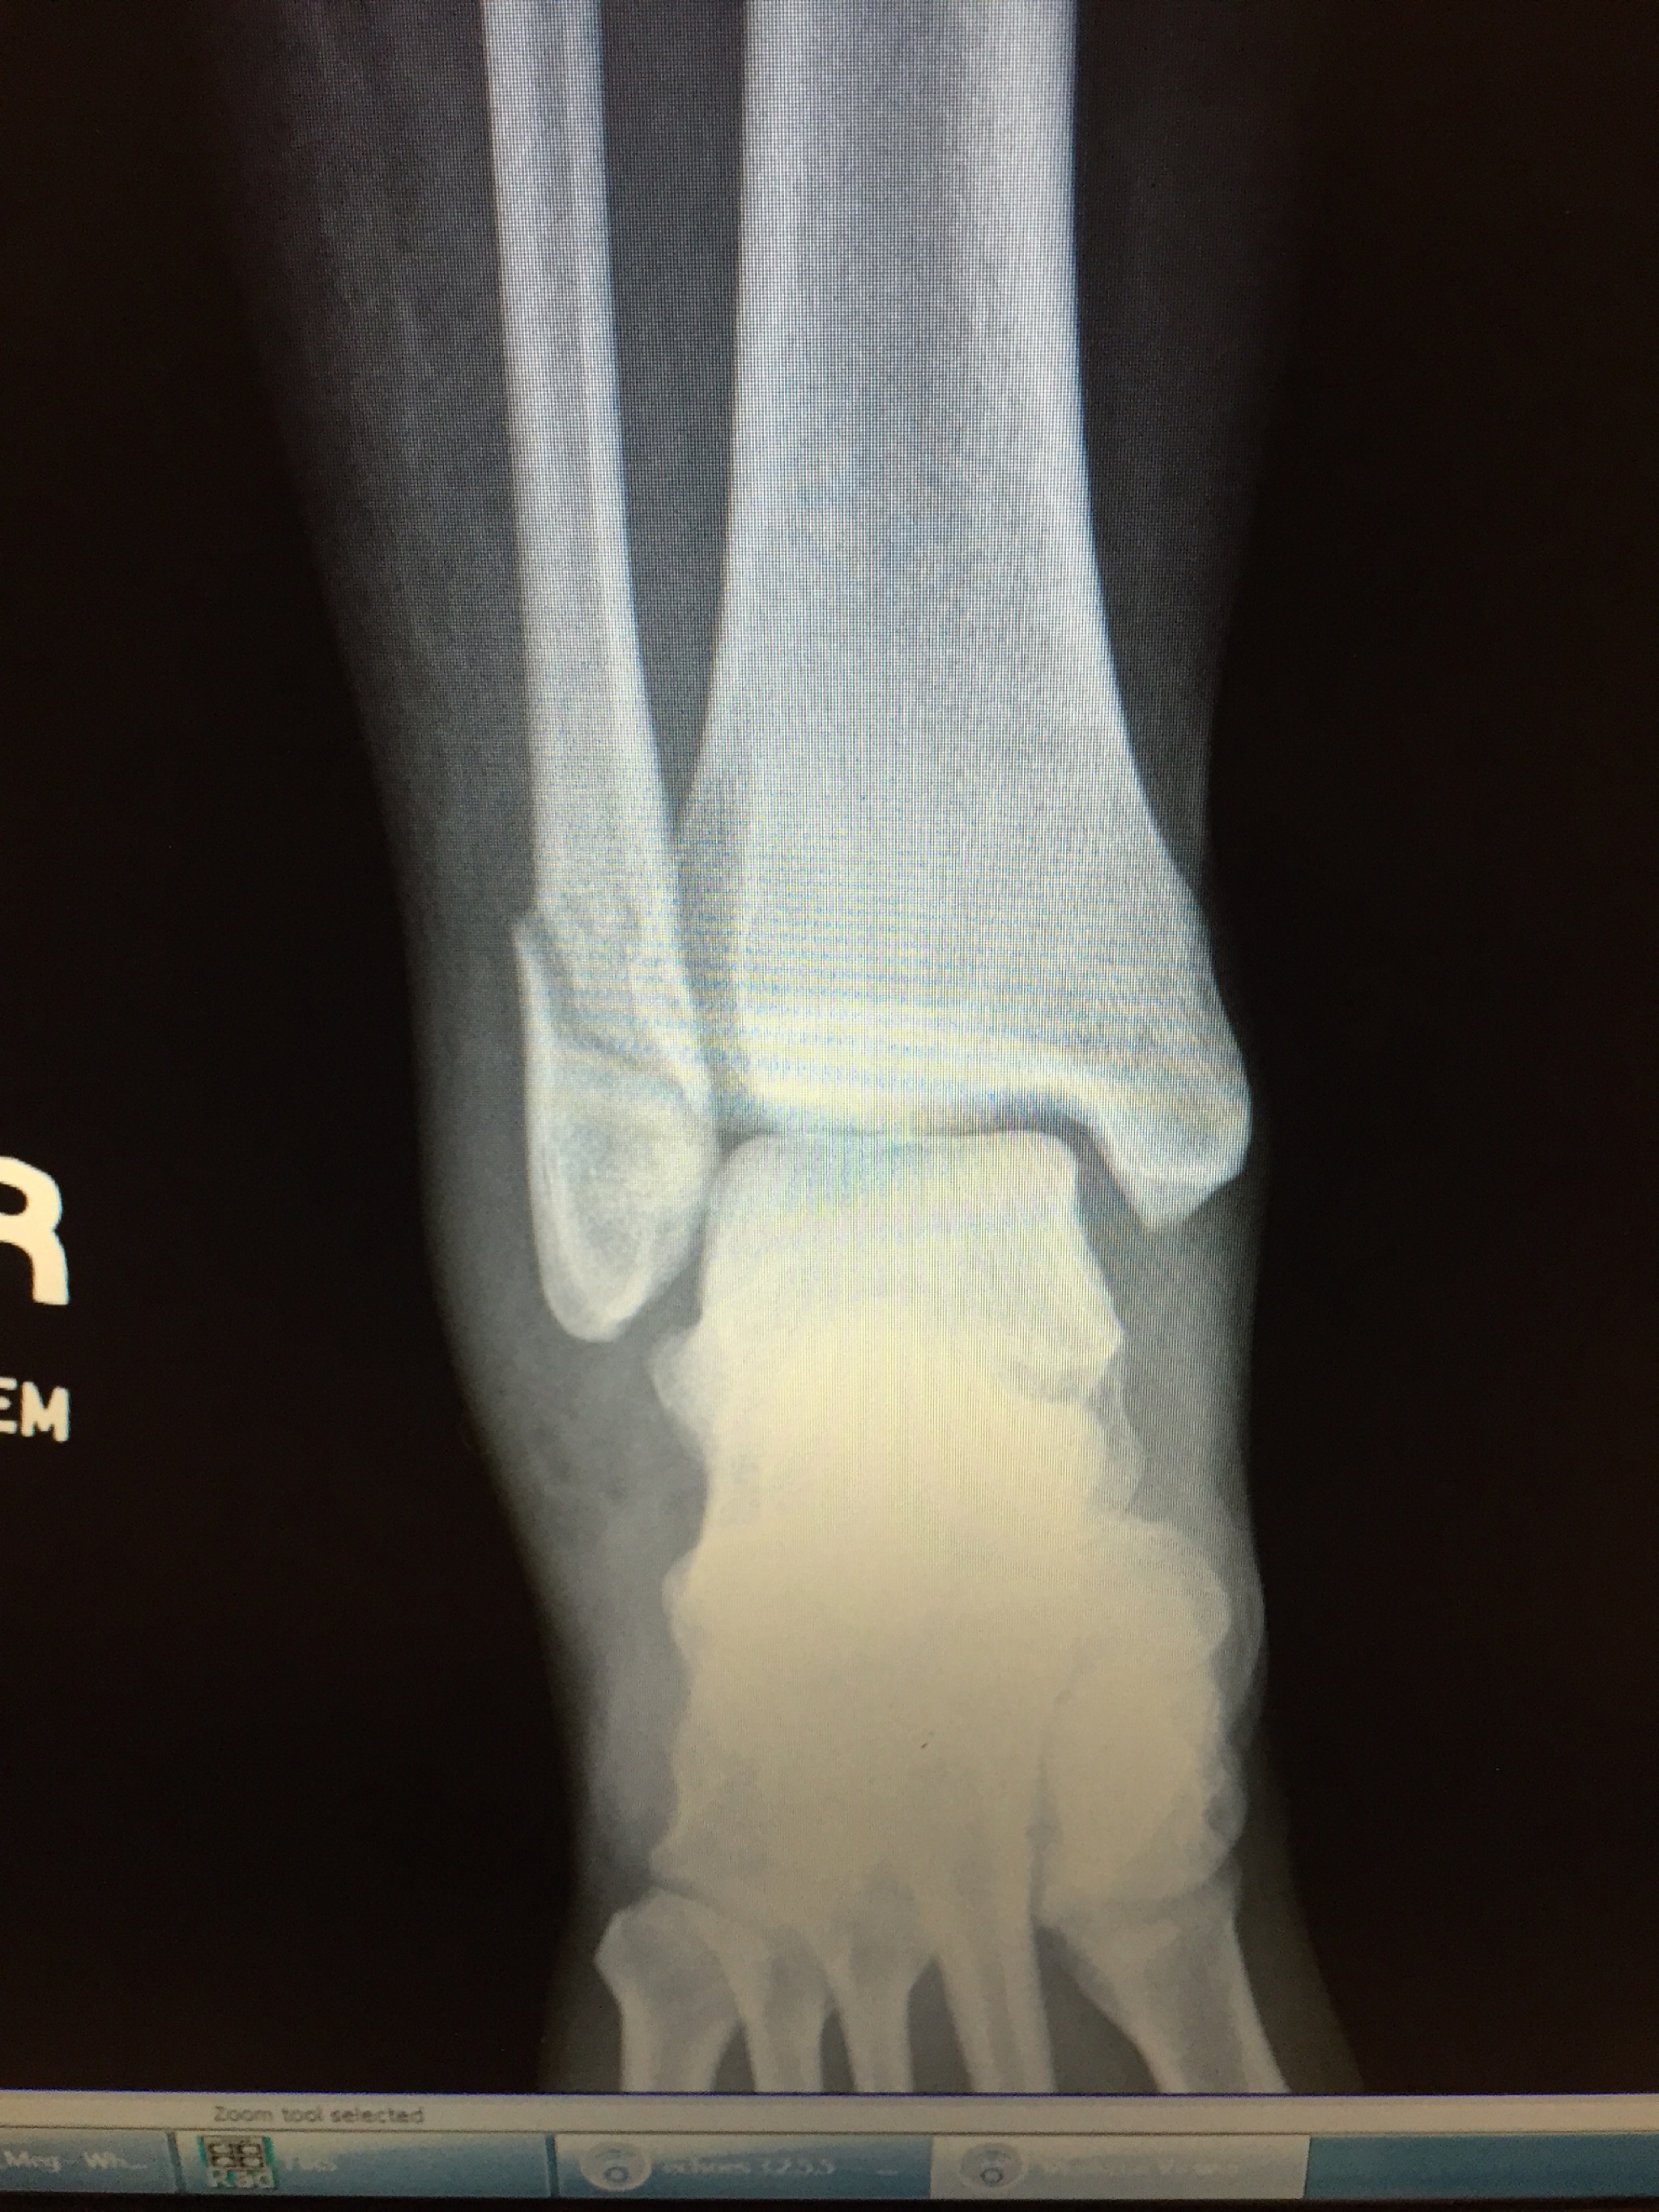

About the same time I started feeling better, Brian and I went to a family function of ours. We were playing kickball with his younger cousins, and I was chasing around one of the girls, being silly. My graceful nature interceded when I slipped on some dewy grass, and promptly landed poorly on my leg.

I heard it crack and I knew this wasn’t good.

Sure enough, I did a number on it. At this point, I was only seven weeks pregnant, and had broken and displaced the small bone in my leg enough to be a candidate for surgery. Because of the baby, the doctor didn’t want to operate, so nine very-long weeks in a cast and boot followed. The doctor has suggested that I might need surgery after I deliver little “nug”, as Brian and I have been addressing him/her.